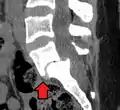

MRI of L5-S1 anterolisthesis

Magnetic Resonance Imaging (MRI)

Magnetic resonance imaging is the preferred advanced imaging technique for evaluation of spondylolisthesis.[30] Preference is due to effectiveness, lack of radiation exposure, and ability to evaluate for soft tissue abnormalities and spinal canal involvement.[30][31] MRI is limited in its ability to evaluate fractures in great detail, compared to other advanced imaging modalities.[32]